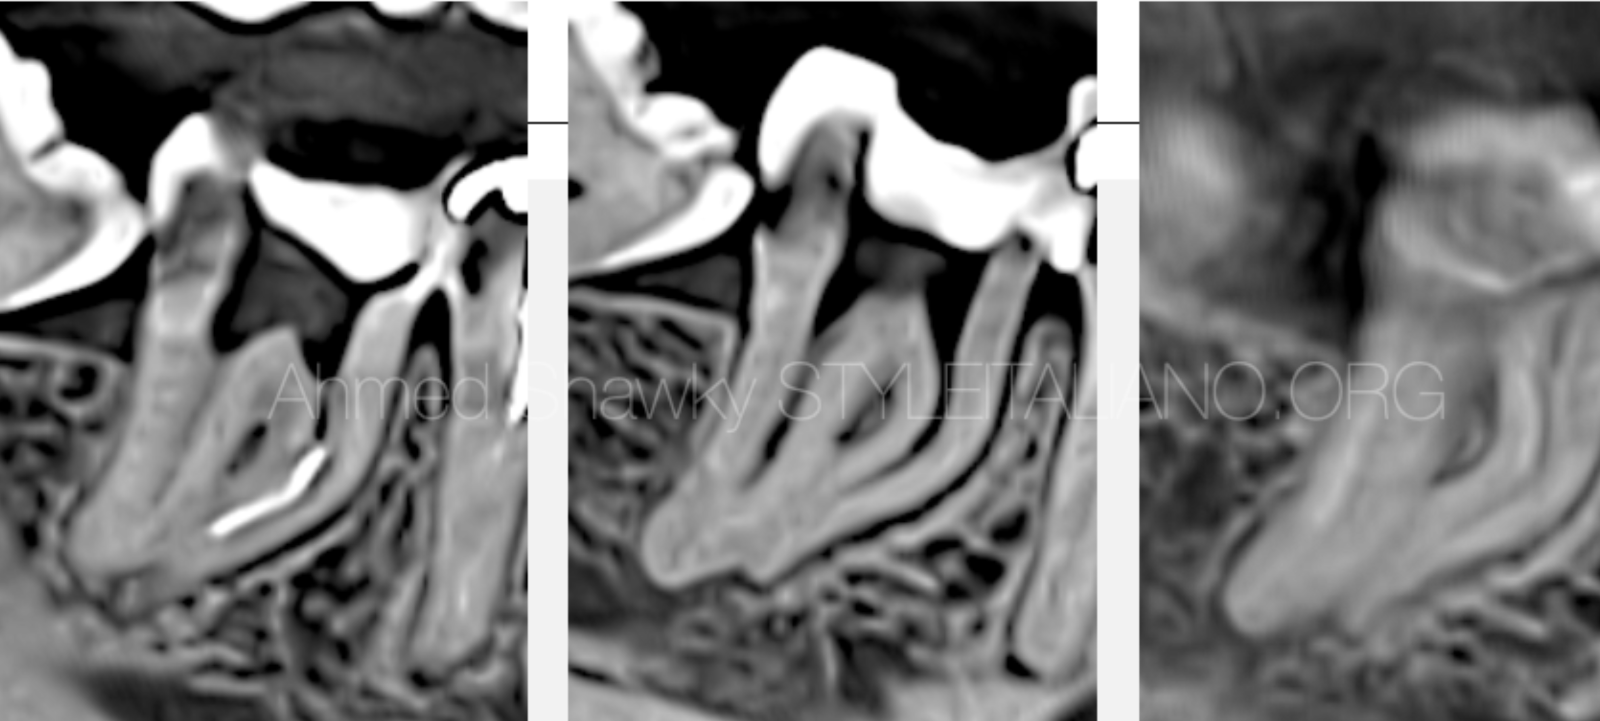

2D and CBCT evaluation revealed a small hand file separated in the ML canal, CBCT was mandatory to plan the retrieval approaching relevance to the respective anatomy.

The configuration of the mesial root canal system was shown to have multi-planar curvatures, highlighting the reason for file separation

The instrument probably separated due to the improper shaping strategy followed for shaping of the double curved mesial root canals.

It has be emphasized that, For safe and predictable shaping of double curvatures, the clinician should adopt a “Pressureless Crown-down approach”, to address different parts of the multi-planar curvature. The most important step in that approach, is the coronal pre-flaring, which can be safely performed mechanically to eliminate severe coronal dentin resistance. Such dentinal resistance, can be a reason for file separation in the coronal and middle portions, as in this case.